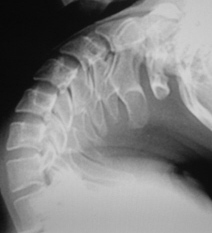

Иллюстрации 5, 6, 7. Определяется выраженная «сглаженность» шейного лордоза на уровне С2-С6. Определяется некоторая скошенность передне-верхних лимбусов тел С4, С5. В положении разгибания определяется смещение кзади тел С3, С4, С5 в виде лестничной комбинации, что свидетельствует о нестабильности в сегментах С3-С4, С4-С5, С5-С6 и указывает на дистрофические изменения в межпозвонковых дисках указанных сегментов.

Иллюстрация 7 – фрагмент с увеличением, на котором четко определяется смещение кзади тел позвонков.